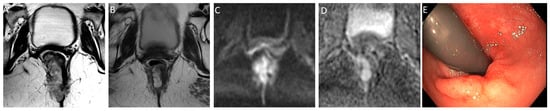

- CR signifies the remarkable disappearance of T2 intermediate signal, indicating a significant reduction in tumor size and suggesting a highly favorable response to treatment. Changes in T2-weighted imaging and DWI pertaining to CR are described below and exemplified in Figure 2:

- T2-weighted imaging—In T2-weighted imaging, CR can be represented as a linear or crescent-shaped scar within the mucosal/ submucosal layers or even the normalization of the rectal wall. It is known that rectal wall normalization can be seen in 5% of cases and is suggestive of CR [64].

- DWI—CR on DWI is characterized by the absence of high signal intensity on high b-value DW images [65,66,67,68]. It is essential to compare DW images at restaging with baseline images and with the normal rectum as references. This can be especially valuable in identifying CR in small, subcircumferential scars [69].